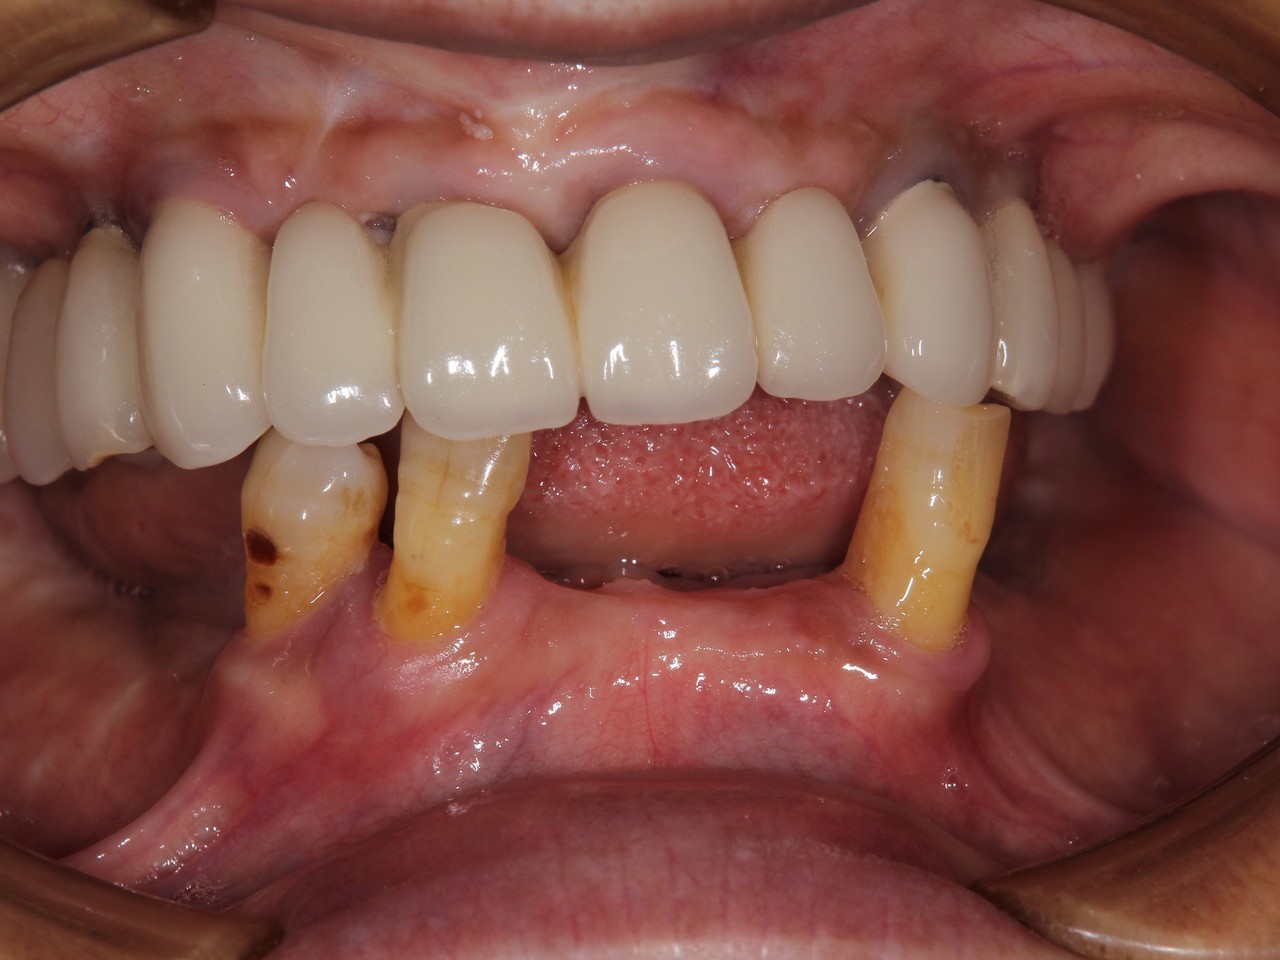

歯周病とインプラント(抜歯即時荷重)<ガイドシステムを使用した埋入法>

インプラント8本で14本の歯を並べたケース・仮歯代含む (函南町在住 女性

抜歯後、片顎8本のインプラントを埋入し、即日に仮歯を製作する事により、1日で片顎14本の歯を回復します。事前にインプラントを埋入する位置をCTによりシミュレーションし、埋入ガイド、仮歯を準備したうえで手術を行います。埋入ガイドにより、正確な位置にインプラントを埋入することができます。

治療の流れ

治療前

下の歯は歯周病でグラグラです。

後のインプラント手術時に、抜歯します。